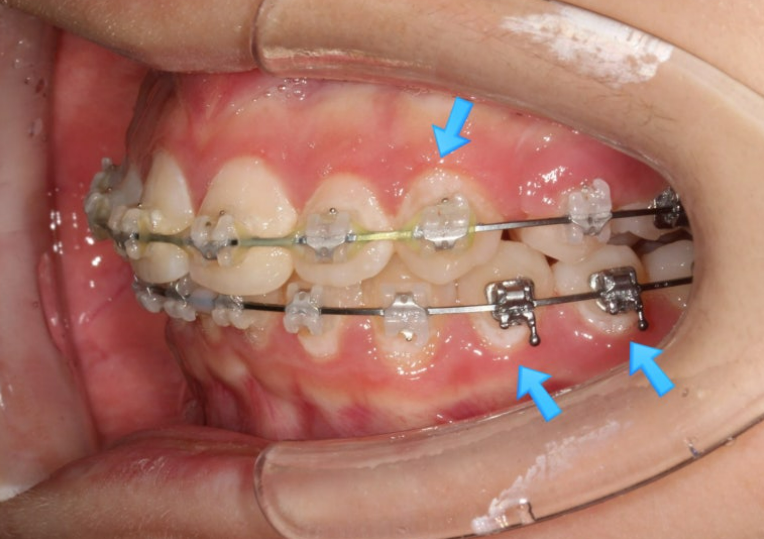

치료시작 9개월째 모습입니다.

파란 화살표의 브라켓 주변 희끗한 부분은 양치가 잘 안되어 탈회된 부분입니다.

치아가 삭았다라고도 하고 정체는 초기충치입니다.

클리피씨 교정은 인비절라인과 다르게 양치질 할 때 장치 및 설차 주변을 깨끗하게 닦기가 힘듭니다.

충치가 많고 양치질이 잘 안되는 분들에게는 같은 진단이라면 클리피씨보다 인비절라인을 더 권유하는 이유입니다.

이런 초기충치가 보이는 환자분들께는 불소도포를 주기적으로 해주고 양치질 교육에 힘쓰고 있습니다.